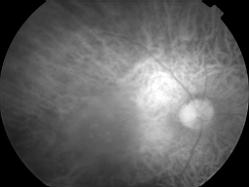

DMLA associant un DSNE et une plage de NVO